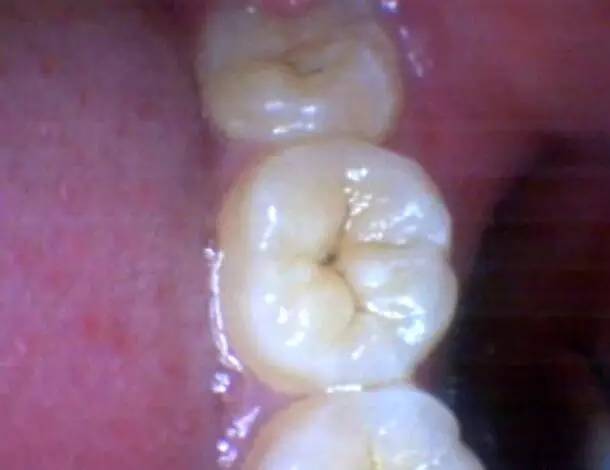

这是前不久来门诊的一位患者,去美国上大学前来看牙。

当时把这个牙齿图给他看,告诉他这个情况需要补牙时,他反问了好几次:这个真的需要补牙吗?